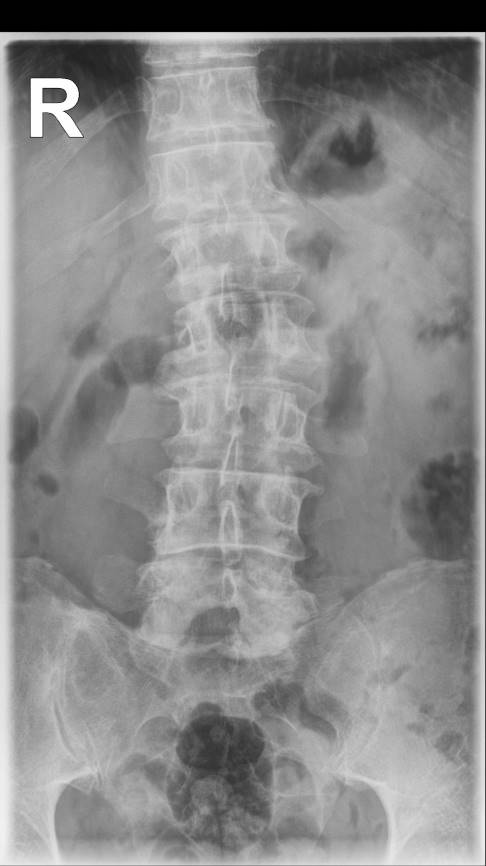

Bei der körperlichen Untersuchung zeigt sich in der Regel eine deutliche seitliche Verbiegung der Wirbelsäule. Eine Skoliose liegt ab einer seitlichen Verkrümmung der Wirbelsäule von 10 Grad vor. Diese wird anhand des Cobb-Winkels gemessen, den der Rückenspezialist im Röntgenbild bestimmen kann. Die Prognose bei frühzeitiger Therapie ist meist recht gut.

Bei Skoliosen im Lendenbereich sind die beiden Dreiecke zwischen der Taille und den seitlich am Rumpf herunterhängenden Armen (= Taillendreiecke) unterschiedlich ausgebildet. Es besteht ein Lendenwulst auf der krümmungsabgewandten Seite. Mithilfe der Röntgenuntersuchung kann der Arzt die Form und das Ausmaß der Skoliose beurteilen.

Die Stärke der Krümmung der Wirbelsäule ermittelt er über eine besondere Winkelmessung nach Cobb. Darüber hinaus beurteilt der Arzt den Torsionsgrad (Grad der Verdrehung) anhand der Pedikelschatten im Röntgenbild. Als Pedikel bezeichnet der Mediziner den Übergang zwischen Wirbelkörper und Wirbelbogen auf der Rückseite des Wirbels. In unserer Praxis wird mittels einer laseroptischen, dreidimensionalen Wirbelsäulenrekonstruktion die Gesamtausprägung der Skoliose auf das kleinste Detail berechnet. Darüber hinaus können auf diese Weise Röntgenbilder und damit die Strahlenbelastung bei Kindern erheblich eingespart werden.